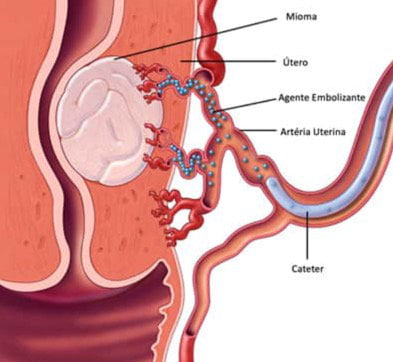

A embolização das artérias uterinas é um método minimamente invasivo realizado por médico radiologista intervencionista que consiste no bloqueio intencional das artérias que nutrem os miomas, provocando, dessa maneira, redução do fluxo de sangue ao mioma e redução dele. Como o efeito da embolização do mioma uterino pode alterar a fertilidade, por causa da redução de fluxo no ovário, a embolização é normalmente oferecida a mulheres que não desejam mais engravidar ou que desejam e precisam evitar uma histerectomia, que é a operação para remover o útero.